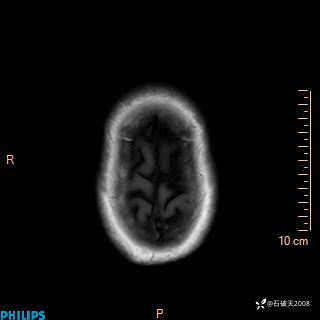

2020.11.14MR

DWI